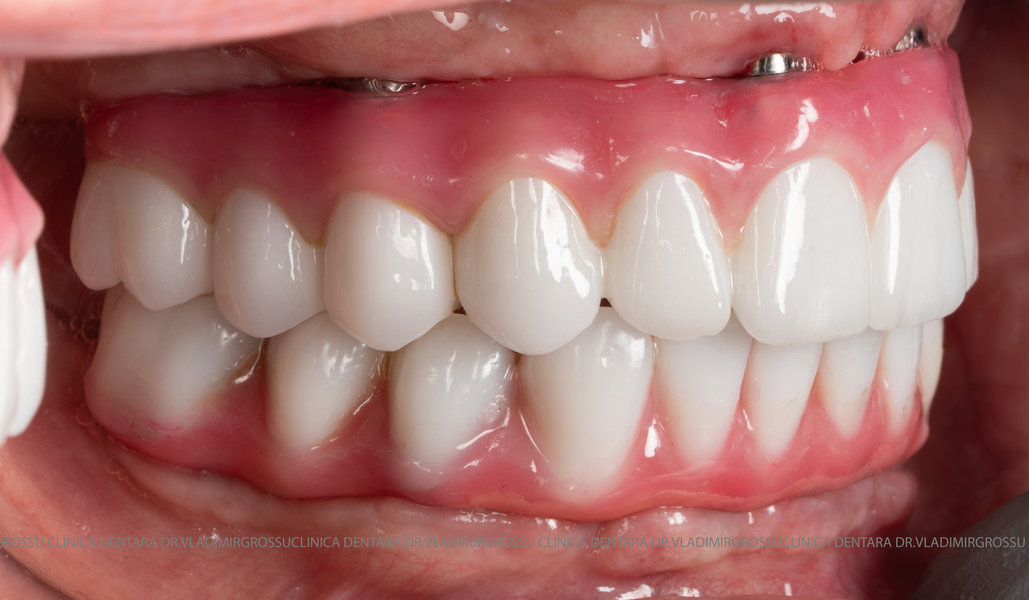

- Posibilitatea realizării unei proteze cu 12-14 dinți, oferind un aspect estetic natural și funcționalitate optimă.

Pentru protezarea definitivă:

- Șase abutment-uri permanente pe multiunit-uri;

- Proteză definitivă realizată din metaloceramică sau zirconiu, cu 12-14 unități (soluția recomandată).

Pentru pacienții cu edentație extinsă sau dinți nefuncționali, metoda All-on-6 oferă o alternativă modernă și eficientă la proteza mobilă, asigurând o restaurare fixă, stabilă și estetică a danturii. Datorită distribuirii optime a implanturilor și a tehnologiei avansate implicate, această soluție îmbunătățește considerabil calitatea vieții, confortul și funcționalitatea orală. Succesul tratamentului depinde de o planificare riguroasă, de utilizarea componentelor de calitate și de competența echipei medicale, ceea ce face ca alegerea unei clinici specializate să fie esențială pentru obținerea unor rezultate durabile și sigure.